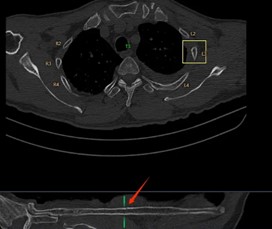

在一些大型醫(yī)院和醫(yī)療研究機(jī)構(gòu),已經(jīng)開始嘗試這種協(xié)作模式。例如,在胸部CT肺結(jié)節(jié)以及肋骨骨折的影像診斷中,AI 首先對影像進(jìn)行分析,標(biāo)記出可能的異常區(qū)域,醫(yī)生再對這些區(qū)域進(jìn)行詳細(xì)觀察和診斷。通過這種協(xié)作,不僅提高了診斷效率,還提升了診斷的準(zhǔn)確性。